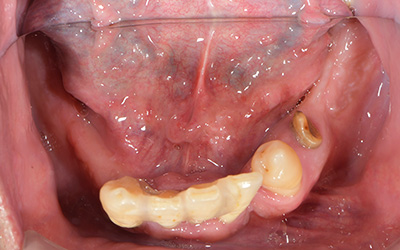

【歯周病で多数歯欠損②】とにかく入れ歯をやめたい!上オールオン6・下オールオン4の患者様

患者さま情報:40代 男性

治療期間:11ヶ月

治療費:5,082,000円(税込)

リスク:骨が足りない場合は骨を足す骨造成が必要です。

副作用:手術により腫れや痛みを伴う場合があります。

before

after